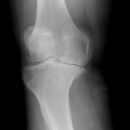

Kniegelenk